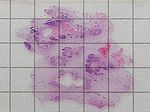

Chron. skleros. kalz. Pankreatitis, HE